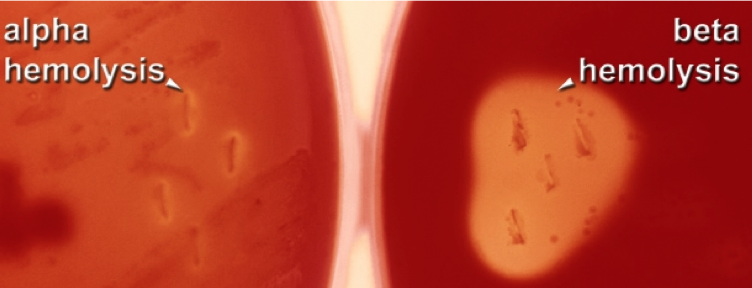

complete hemolysis refers to ___-hemolysis

complete hemolysis refers to β-hemolysis

What type of hemolysis is present?

β-hemolysis

alpha toxin from Staphylococcus aureus produces ___-hemolysis